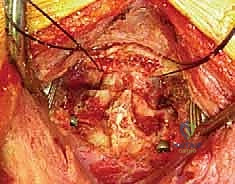

الإجراء الجراحي خطوة بخطوة: داخل غرفة العمليات مع الأستاذ الدكتور محمد هطيف

تُعرف التقنية الأكثر شيوعاً وفعالية اليوم باسم تقنية هارمز/جويل (Harms/Goel Technique)، والتي تتضمن وضع مسامير في الكتل المفصلية للفقرة C1 ومسامير في عنيقة أو جزء (Pars) الفقرة C2، ثم ربطها بقضبان معدنية. يتطلب هذا الإجراء مهارة جراحية فائقة، استخدام الميكروسكوب الجراحي، والتوجيه بالأشعة السينية داخل غرفة العمليات.

الخطوة 2: الشق الجراحي والتعرض

يقوم الدكتور هطيف بعمل شق جراحي دقيق في منتصف الجزء الخلفي من الرقبة. يتم إبعاد العضلات برفق للوصول إلى العظام الخلفية للفقرتين C1 و C2. هنا، تبرز أهمية الجراحة الميكروسكوبية لتقليل النزيف والحفاظ على الأنسجة المحيطة.

الخطوة 3: تحديد المعالم التشريحية وحماية الشريان الفقري

هذه هي الخطوة الأكثر حساسية. باستخدام أدوات دقيقة جداً وتحت تكبير الميكروسكوب، يتم تحديد الحواف العظمية للفقرة C1 والفقرة C2. يتم تحديد مسار العصب العنقي الثاني (C2 nerve root) وإبعاده بلطف. كما يتم تحديد المنطقة المجاورة للشريان الفقري لضمان بقاء المسامير بعيدة عنه تماماً.

الخطوة 4: إدخال المسامير في الفقرة الأولى (C1 Lateral Mass Screws)

يتم تحديد نقطة الدخول على الكتلة المفصلية للفقرة C1. باستخدام مثقاب عالي السرعة (High-speed burr) ثم مثقاب يدوي دقيق، يتم عمل مسار للمسمار. يتم توجيه المسار بدقة ليكون موازياً للقوس الأمامي ومتجهاً قليلاً للداخل نحو مركز الفقرة لتجنب الشريان الفقري الذي يقع في الخارج. يتم إدخال مسمار من التيتانيوم (عادة بقطر 3.5 مم) في كل جانب.

الخطوة 5: إدخال المسامير في الفقرة الثانية (C2 Pedicle/Pars Screws)

بنفس الدقة، يتم تحديد نقطة الدخول في الفقرة C2. اعتماداً على التشريح الفردي للمريض (الذي تمت دراسته مسبقاً عبر الأشعة المقطعية)، يختار الدكتور هطيف إما مسار العنيقة (Pedicle) أو مسار الجزء البين مفصلي (Pars). يتم إدخال المسامير بزاوية محددة لضمان أقصى قوة تثبيت دون اختراق القناة الشوكية أو ثقبة الشريان الفقري.

الخطوة 6: تركيب القضبان واستعادة المحاذاة (Reduction)

بعد وضع المسامير الأربعة بنجاح، يتم تقييم وضعية الفقرات. إذا كانت C1 منزلقة للأمام، يتم استخدام أدوات خاصة لسحبها للخلف واستعادة المحاذاة الطبيعية مع C2 (عملية تُسمى Reduction). بمجرد تحقيق الوضعية المثالية، يتم قص قضيبين من التيتانيوم بالطول المناسب وتثبيتهما بقوة في رؤوس المسامير. هذا يخلق "سقالة" معدنية صلبة تمنع أي حركة بين الفقرتين.

الخطوة 7: التصوير الشعاعي داخل العمليات

طوال الإجراء، وخاصة بعد تركيب المسامير والقضبان، يتم استخدام جهاز الأشعة السينية المحمول (C-arm